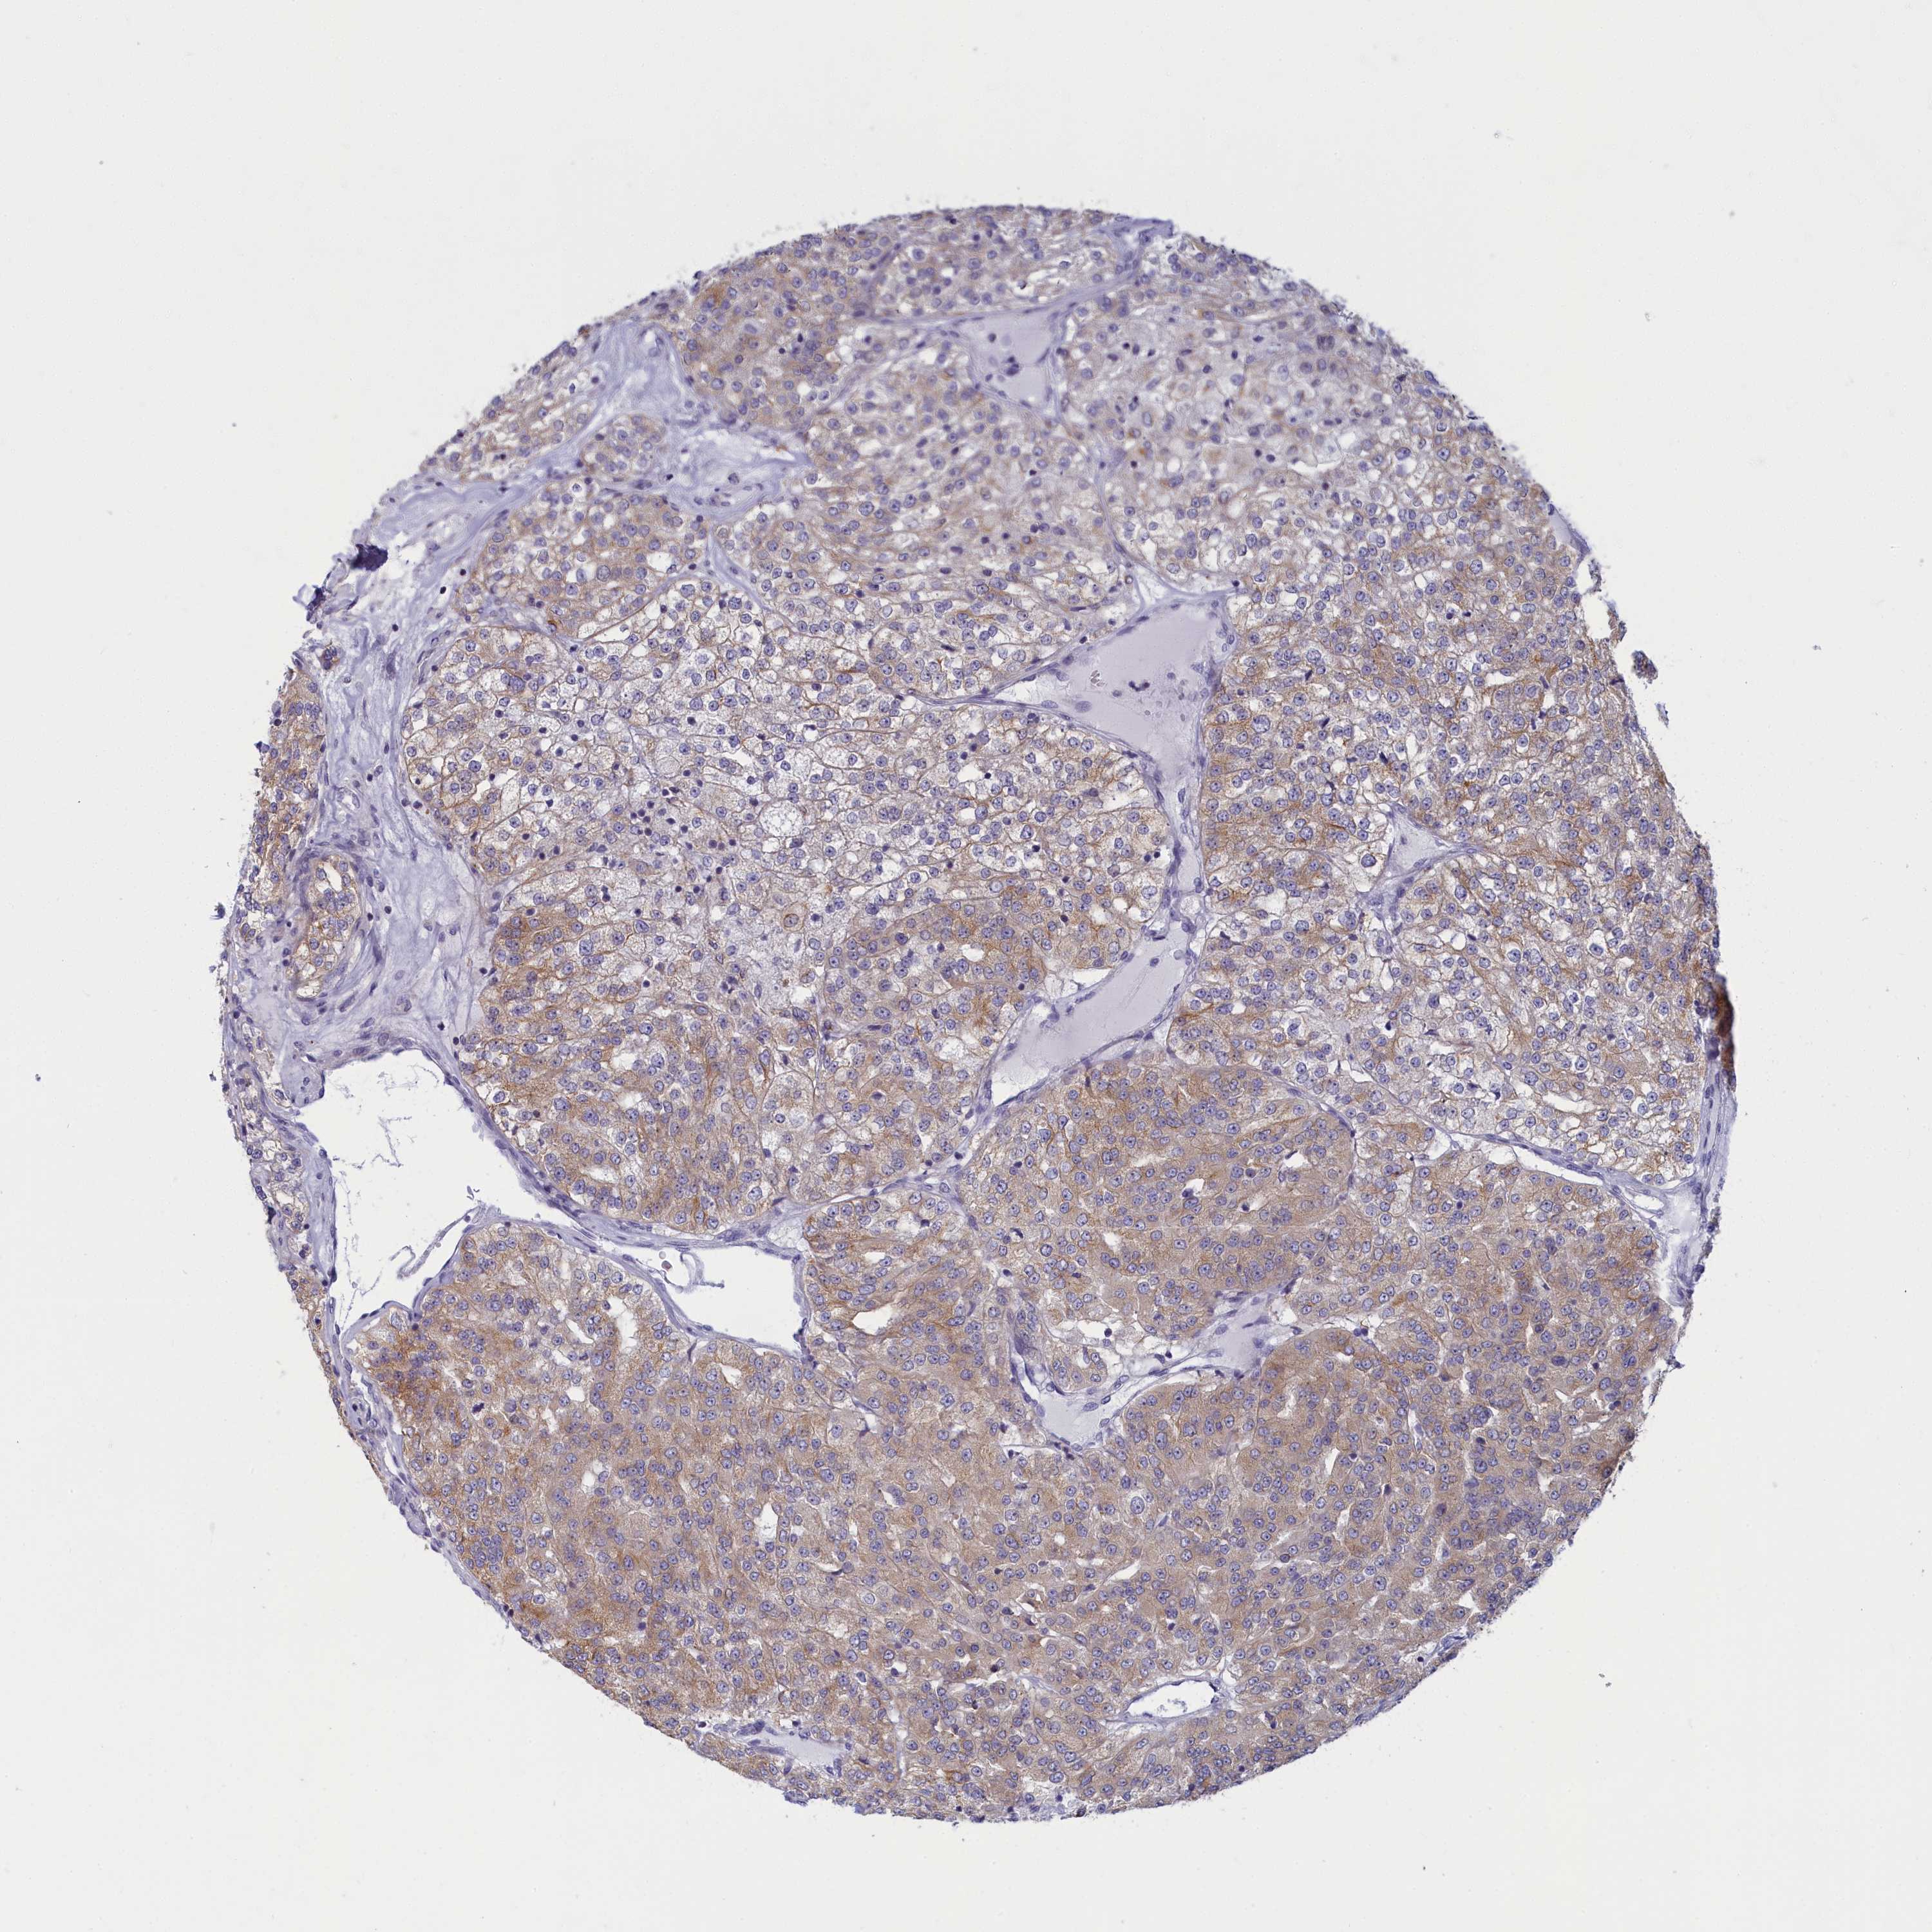

TCGA RNA samplesi

RNA-seq data is reported as average FPKM (number Fragments Per Kilobase of exon per Million reads), generated by the The Cancer Genome Atlas (TCGA) .

Normal distribution across the dataset is visualized with box plots, shown as median and 25th and 75th percentiles. Points are displayed as outliers if they are above or below 1.5 times the interquartile range. FPKM values of the individual samples are presented next to the box plot.

Average pTPM 11.7